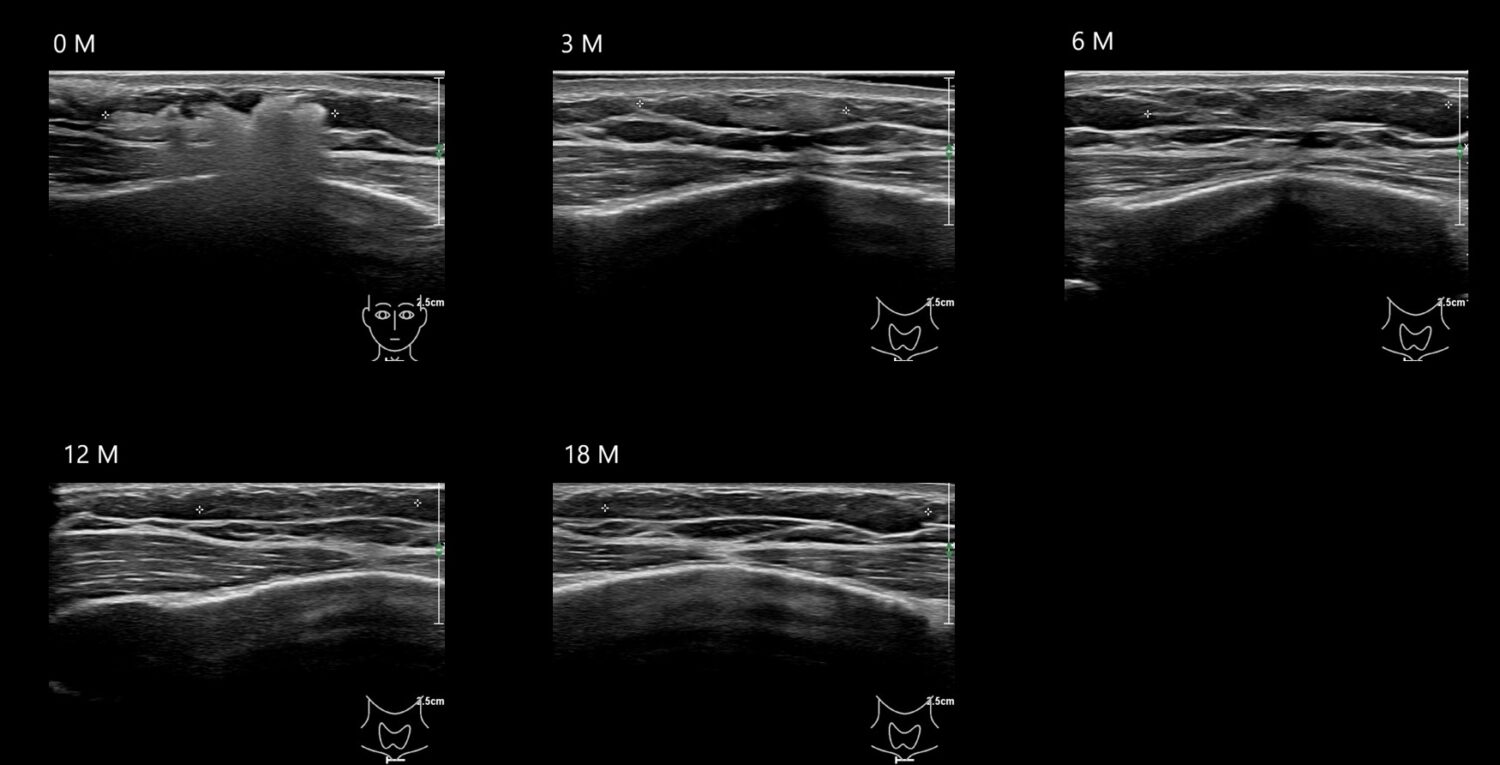

Draw in the image on the right where the fillers are located. To check if your answer is correct, please click on the secondary image.

Draw in the second image below where the fillers are located. To check if your answer is correct, swipe the first image to the right.